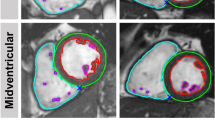

Visual assessment of AI segmentation provided possible explanations for the difference in measurements performed with manual and AI methods. The main observed inaccuracies using AI segmentation were (1) LVOT not included in the volume calculation and hence underestimation of LV volumes, shown in Fig. 3; (2) underfitting of LV endocardial contour which might be another reason for underestimated LV volumes, Fig. 4 Panel B (3) selection of wrong end-diastolic or end-systolic frame for analysis especially when prospective electrocardiographic gating was used for image acquisition Fig. 4; (4) Overestimation as well as suboptimal tracing of RV trabeculations, Fig. 4 Panel C; (5) Errors in excluding RVOT and including RA from RV volumes.

Examples of manual and suboptimal AI myocardial segmentations. Panel A shows an ideal example of manual myocardial contouring using the software, please note that the contours exactly delineate the cardiac chamber structures. Panel B shows an example of slight underfitting LV endocardial contour which might partly explain underestimation of LV volumes. There is also suboptimal segmentation for LV epicardial, and RV endocardial contours. Panel C shows overestimation and suboptimal tracing of RV trabeculations and underfitting of LV endocardial contour in a patient with congenital heart disease